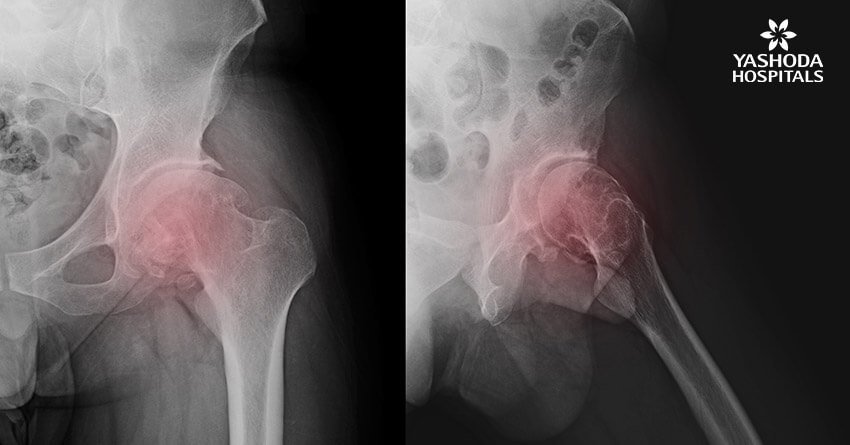

A lack of blood supply to the tissue within the bone leads to its death, a condition called as avascular necrosis or osteonecrosis. It can sometimes lead to tiny breaks within the structure of the bone which is responsible for its eventual collapse. The hip is the most commonly affected area with osteonecrosis. Other than the hip, commonly affected areas are the knee, shoulder, hand and foot.

X-rays: Determine the bone changes in the later stages of avascular necrosis.

MRI: Assess the presence of early changes in bone indicative of avascular necrosis.